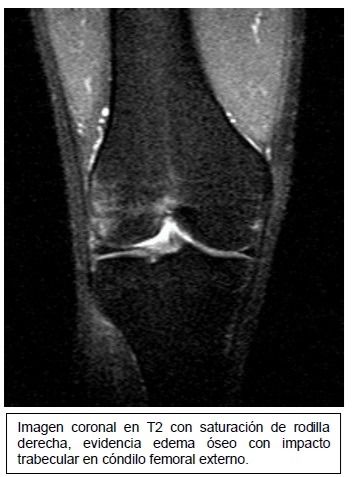

Imagen coronal de secuencia potenciada en T2 con saturación grasa de la rodilla derecha en paciente con lesión por traumatismo en valgo. Edema óseo en la

Fuente: https://epos.myesr.org/posterimage/esr/seram2014/124014/mediagallery/577012